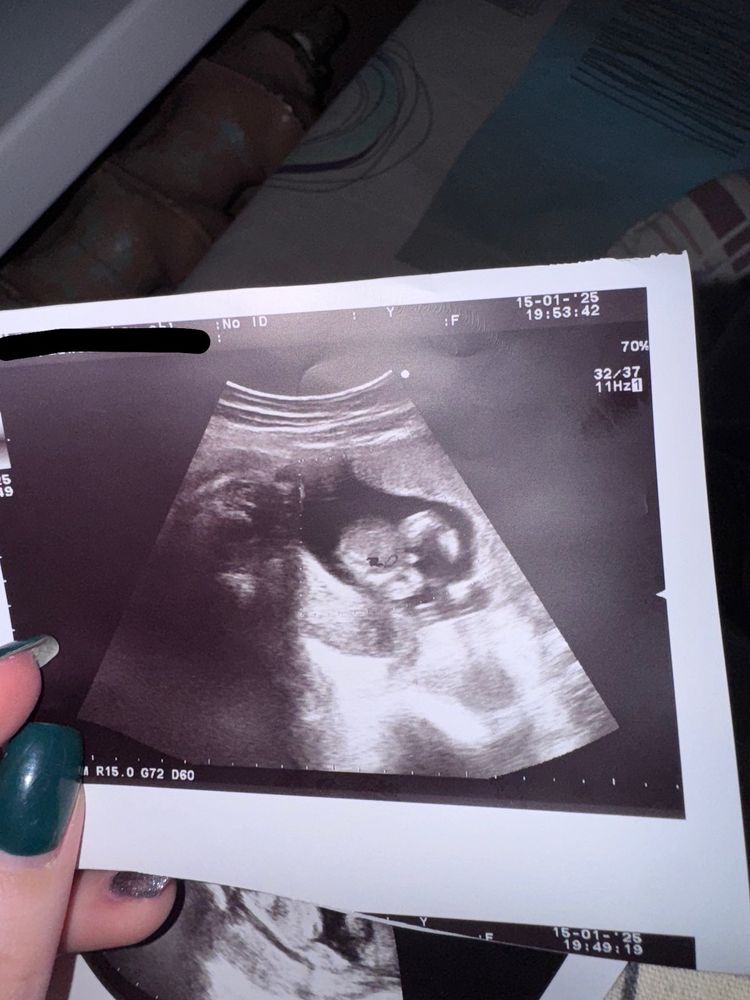

Пол малышаВсем привет, 16 недель, врач сказала что мальчик и дала такое фото.

как считаете это половой орган или пуповина? Девочка или мальчик?

Мне кажется мальчик, видно половой орган 🥹